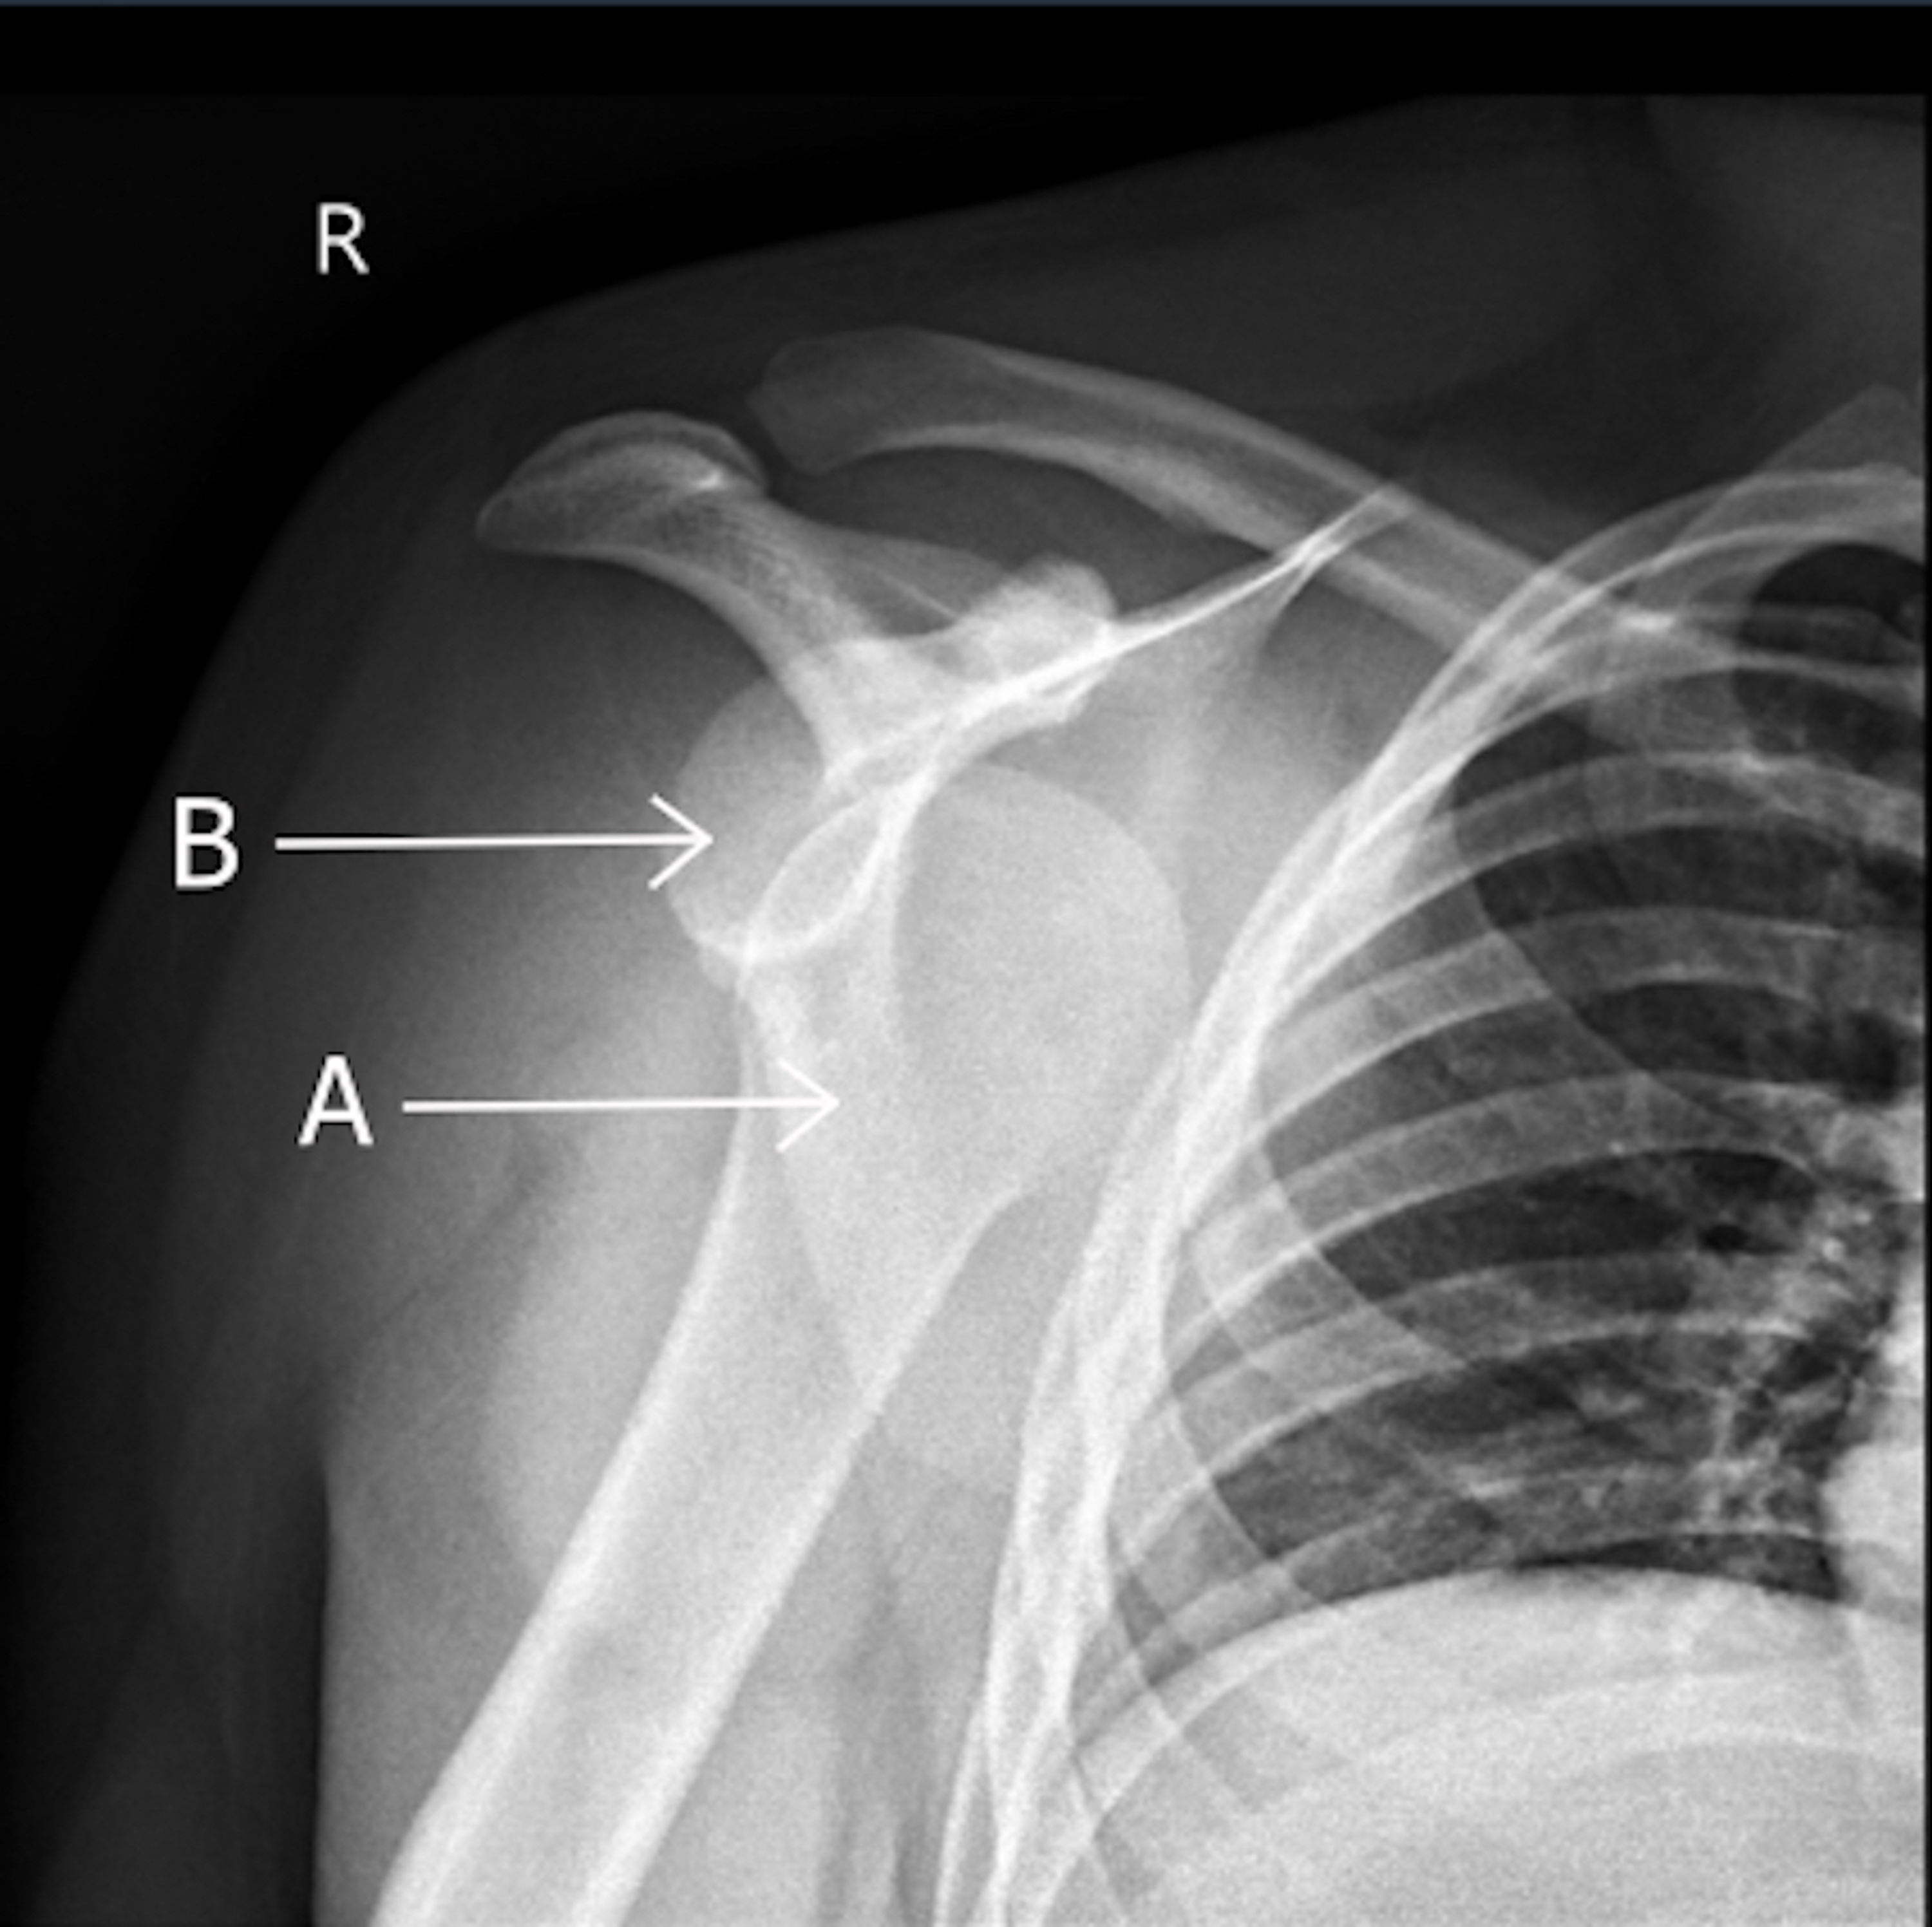

ANTERIOR SHOULDER DISLOCATION WITH FRACTURE Shoulder Joint Fracture X Ray  Sometimes, additional imaging techniques, such as a.   the neer system divides the proximal humerus into four parts and considers not the fracture line, but the displacement as being significant in terms.   diagnosis is made with orthogonal radiographs of the shoulder. The humeral head should be on the glenoid in any other. A patient with a proximal humerus fracture.. Shoulder Joint Fracture X Ray.

ACROMIOCLAVICULAR JOINT INJURY Shoulder Joint Fracture X Ray  Front and side pictures show the swelling and bruising down the arm.   diagnosis is made with orthogonal radiographs of the shoulder. The humeral head should be on the glenoid in any other.   in this review, we will discuss the mechanisms of injury, key imaging findings, therapeutic options and.   the neer system divides the proximal humerus into four. Shoulder Joint Fracture X Ray.